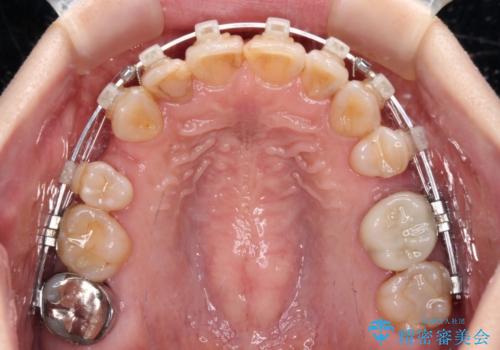

- 矯正装置

- クリアブラケット

第二小臼歯抜歯はイレギュラーな治療となるため、アンカースクリューを補助的に使用して、スムーズに治療を行えるように工夫をしました。